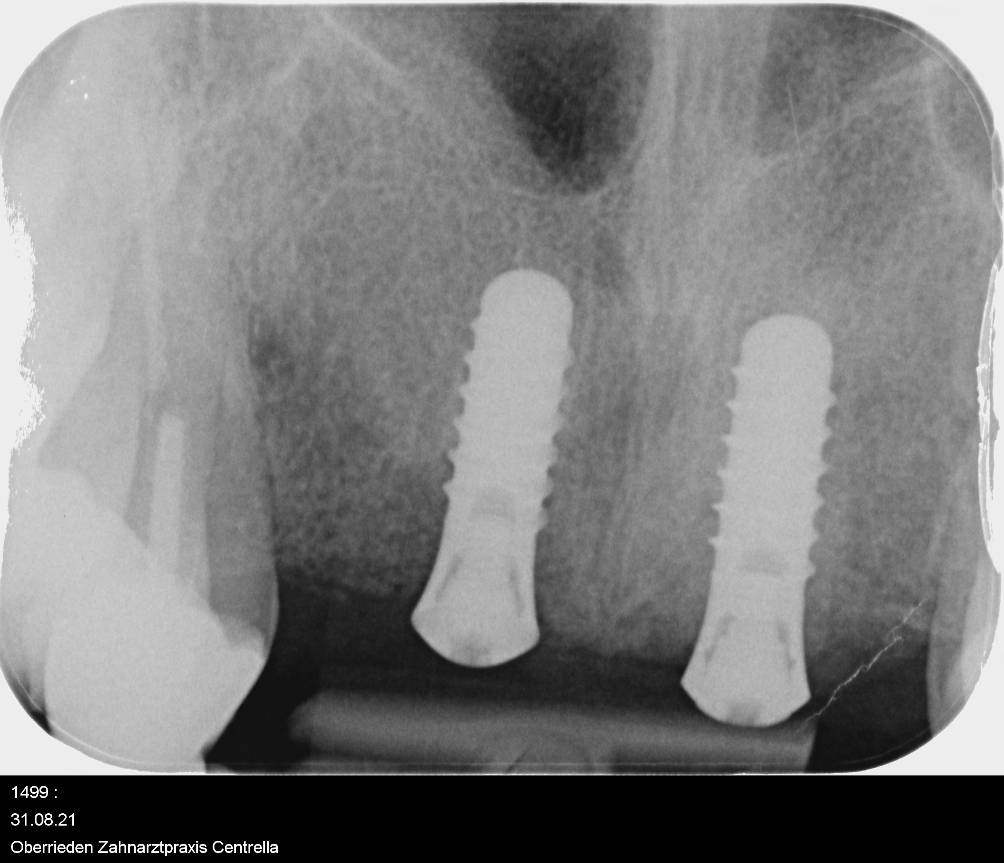

3 Monate später bei der Nachkontrolle - аls ob nie ein Defekt gewesen wäre